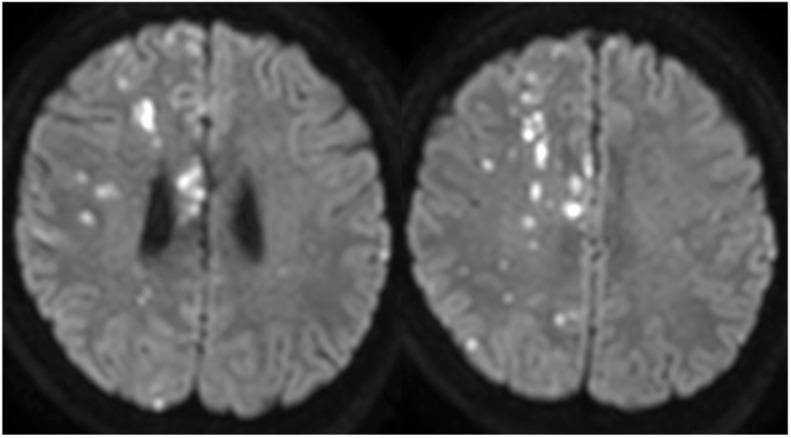

A 51-year-old woman developed subarachnoid hemorrhage the day after transient left hemiparesis. Angiography revealed a ruptured anterior cerebral artery dissecting aneurysm. We conducted stent-assisted coil embolization with the overlapping stent technique on the day after the hemorrhage. She recovered steadily without rebleeding. Six months after embolization, no recurrence was found on angiography.

一名51岁女性在短暂性左侧偏瘫后次日发生蛛网膜下腔出血。血管造影显示大脑前动脉夹层动脉瘤破裂。我们在出血后次日采用重叠支架技术进行了支架辅助弹簧圈栓塞。她恢复平稳,未再出血。栓塞6个月后,血管造影未发现复发。